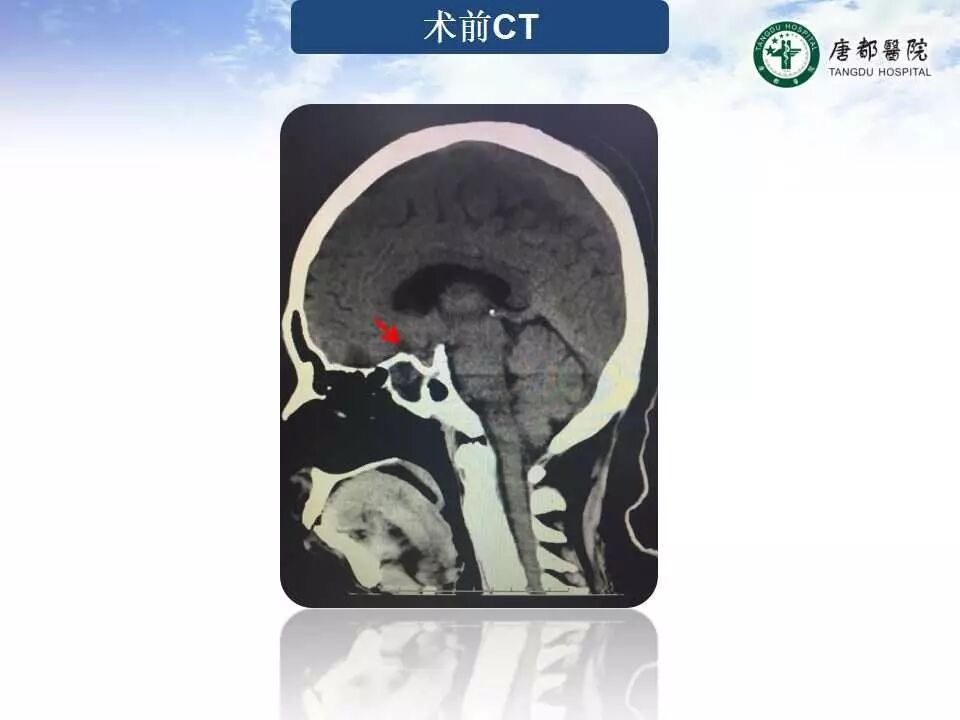

Case 1

长按并识别二维码即可查看该手术视频